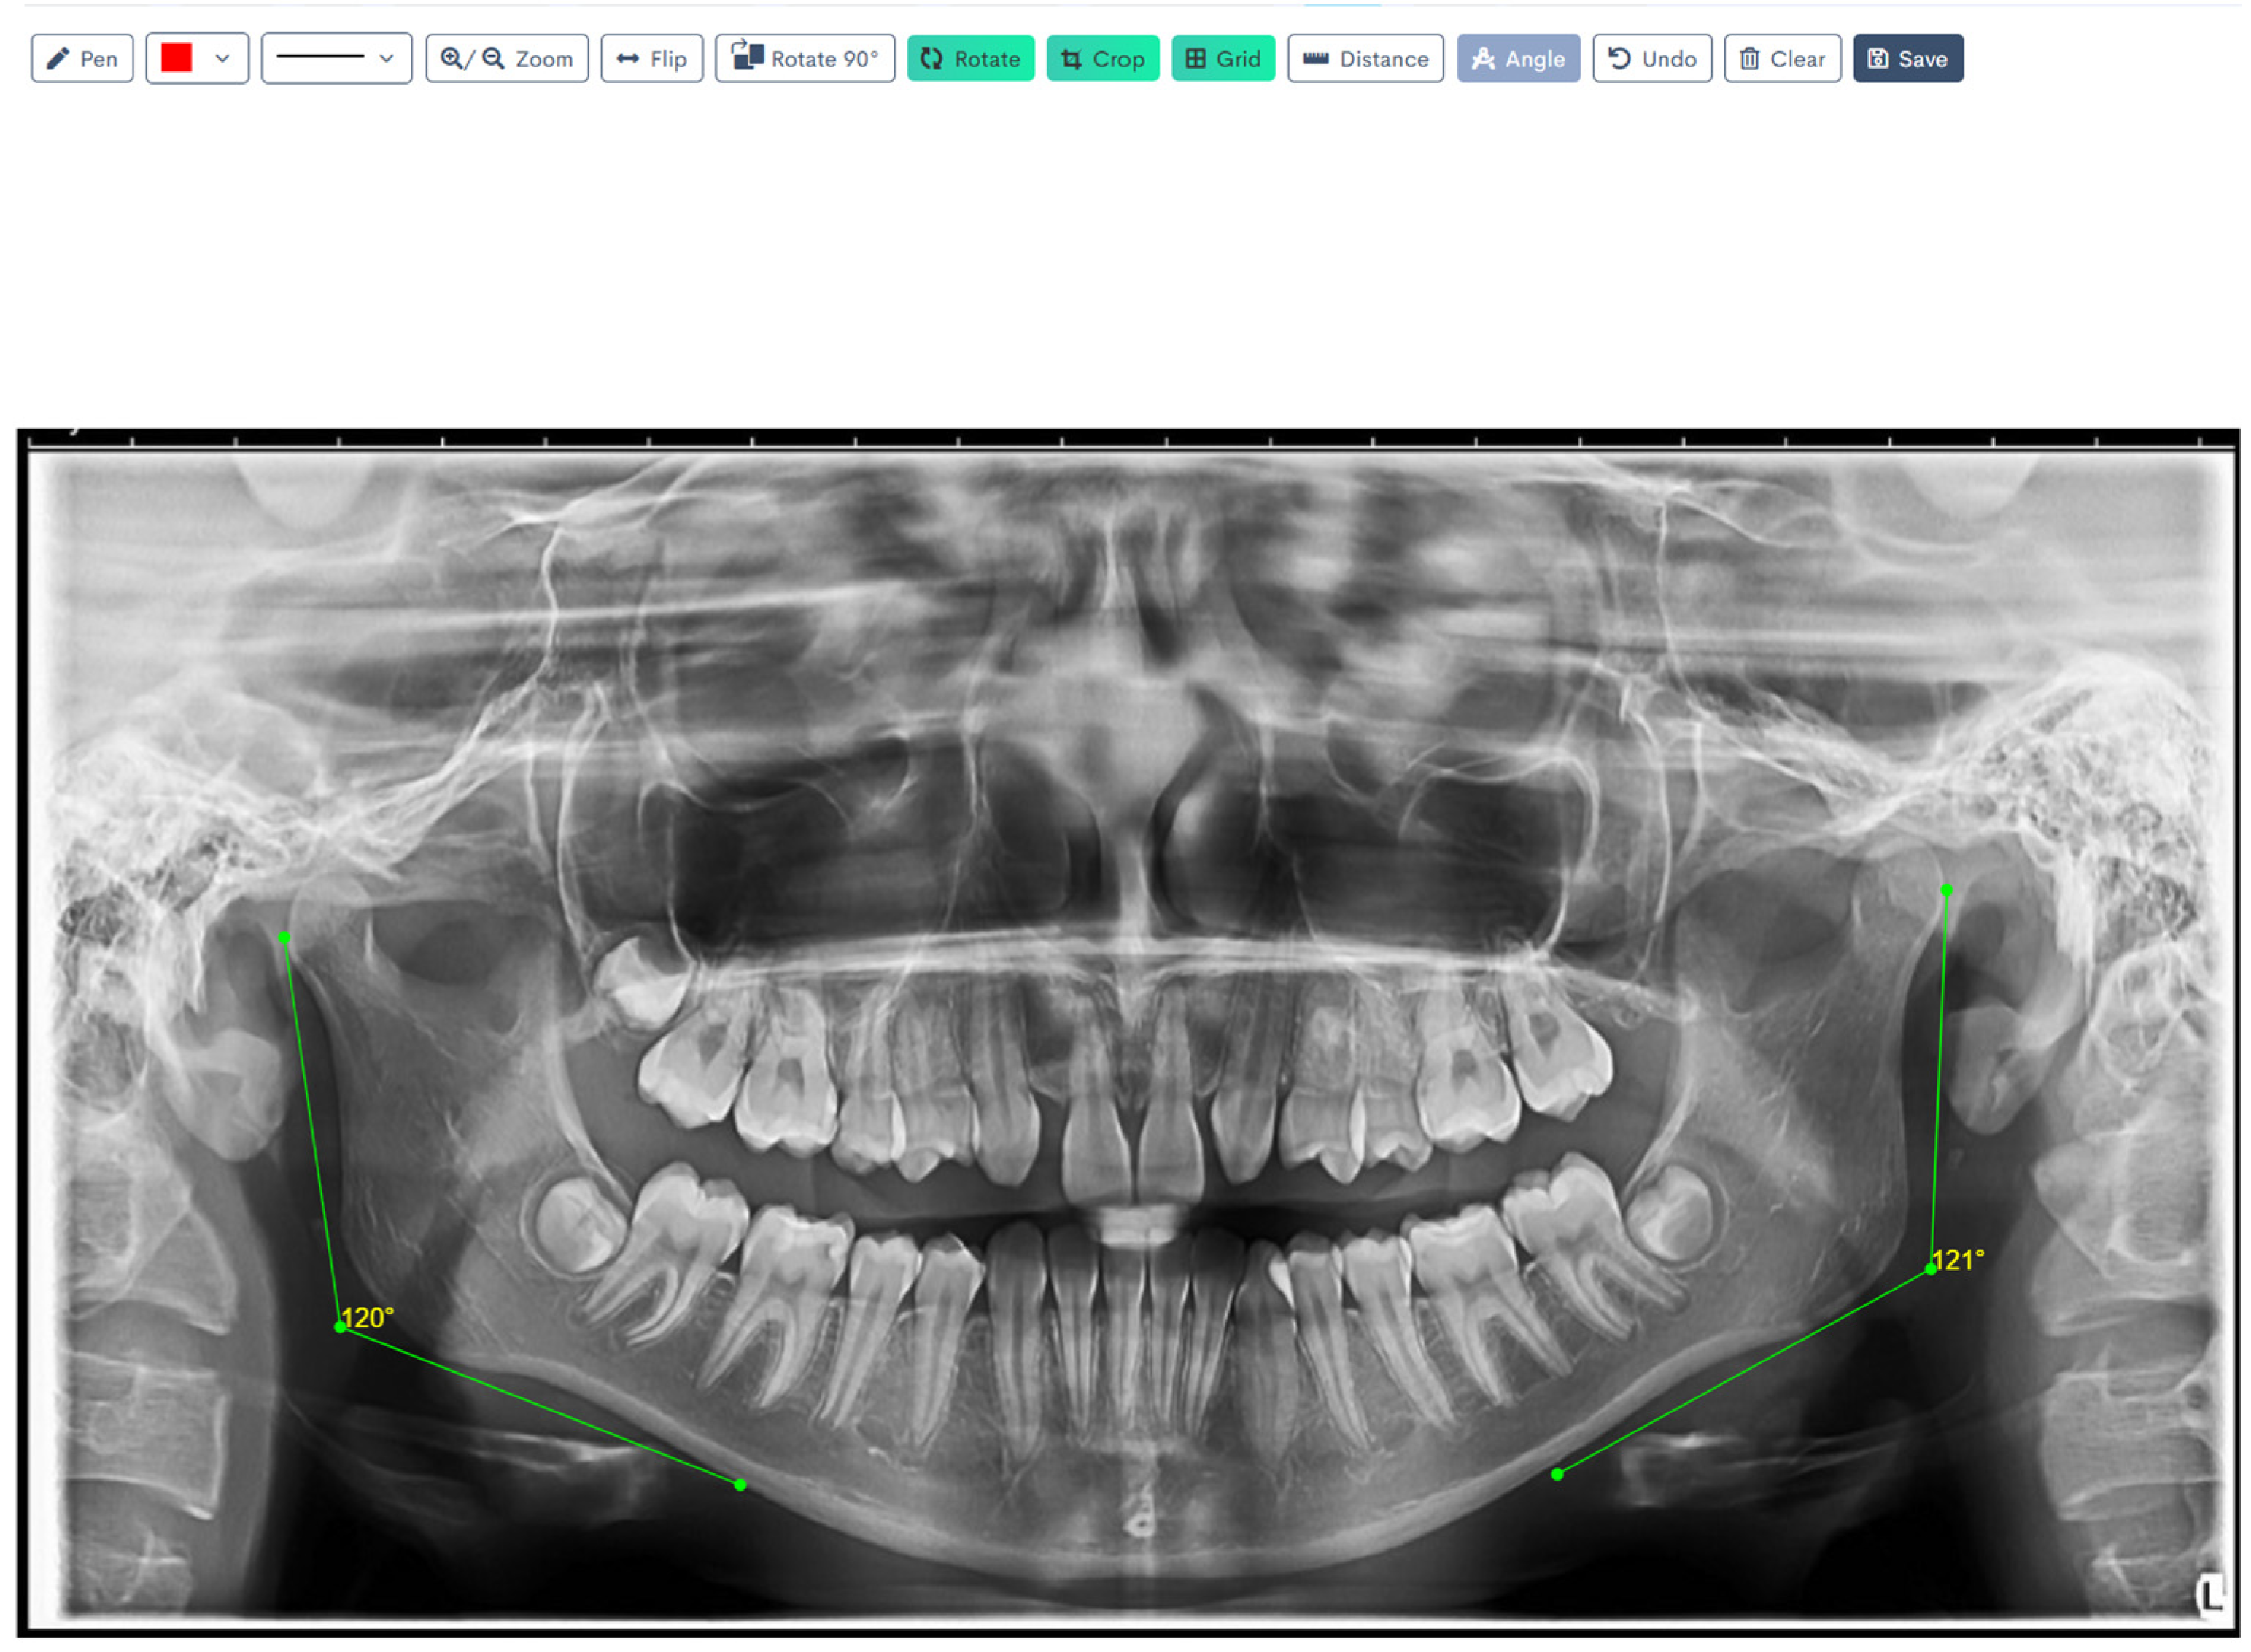

Figure 1, Figure 2, Figure 3, Figure 4, Figure 5 and Figure 6 illustrate the AI-assisted digital measurements exported from the WebCeph software, showing the identification of anatomical landmarks and linear or angular dimensions analyzed in this study.

Digital tracing of bilateral gonial angles was performed directly in WebCeph on a panoramic radiograph, after which the angles were computed from a line along the posterior border of the mandibular ramus and a line along the inferior border of the mandibular body. The left and right gonial angles (shown in green) are displayed with on-screen angle readouts (e.g., 120° and 121°), representing the final measurements obtained through the program’s digital tracing workflow (Figure 4).

Figure 4. Digital Tracing of Bilateral Gonial Angles in WebCeph. Go (gonion)—the most posterior, inferior, and lateral point at the mandibular angle. Tangents drawn along the posterior border of the ramus and the lower border of the mandibular body intersect to form the gonial angle (°). Note: Images represent direct screenshots exported from the WebCeph AI platform. Landmarks and measurement lines were automatically generated and manually verified by the authors.